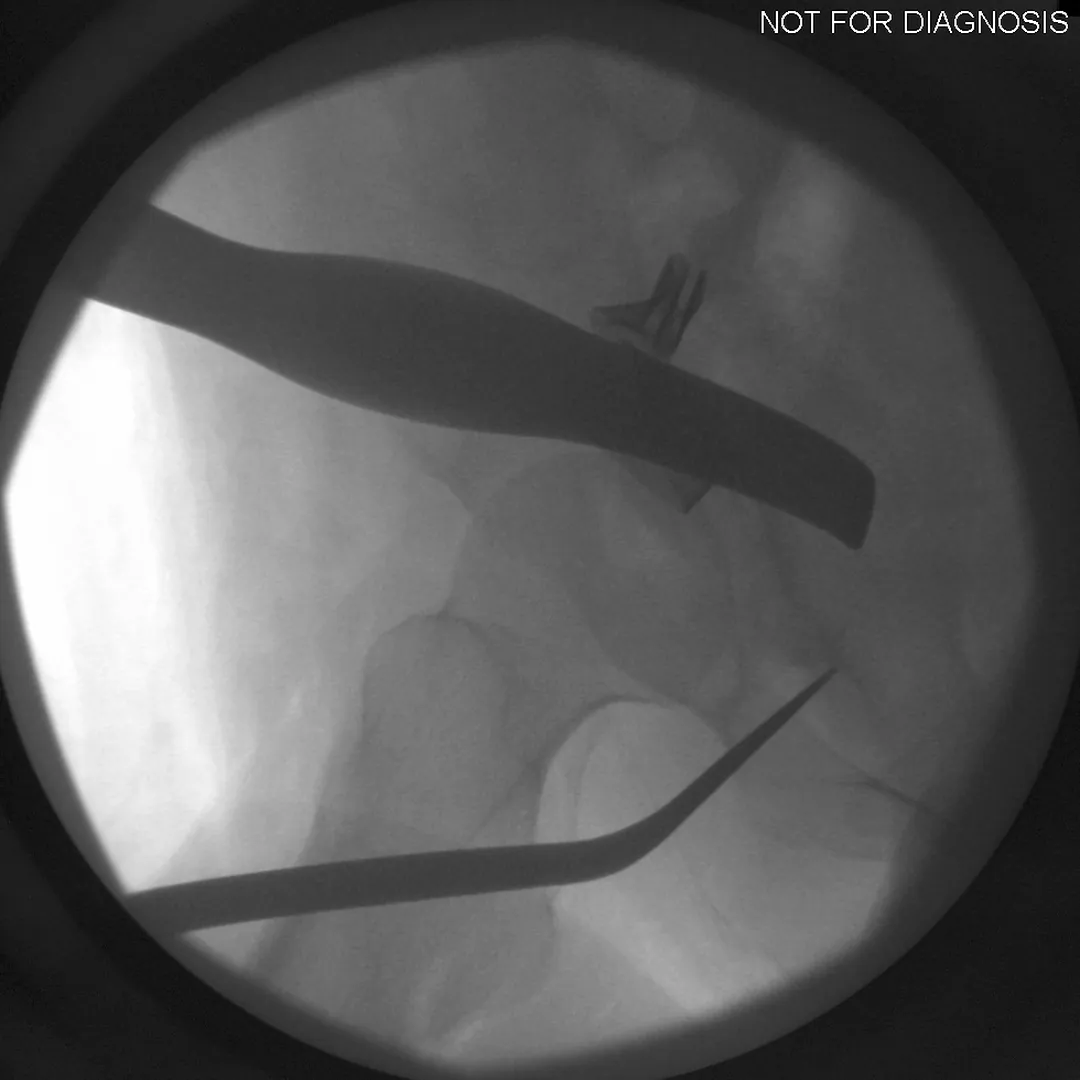

The Surgery

• PAO surgery typically takes 2-4 hours

• It is performed under general anesthesia

• Several controlled bone cuts are made around the hip socket

• The socket is repositioned and fixed with screws

• The hip joint itself is preserved